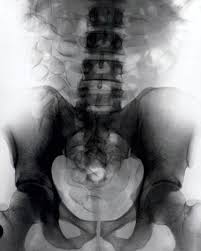

Η ακτινογραφία στην κοιλιακή χώρα του 24χρονου φοιτητή, ο οποίος έφτασε στην Κωνσταντινούπολη από τη Βραζιλία, αποκάλυψε το παράνομο "φορτίο" και οδήγησε στη σύλληψή του.

Ο νεαρός θα δικαστεί στην Κωνσταντινούπολη για παράνομη διακίνηση ναρκωτικών ουσιών. (ΝΕΟ EXPRESS ΤΟΥ ΜΕΣΟΝΥΧΤΙΟΥ ΓΙΑ ΤΟ ... ΒΑΠΟΡΑΚΙ;;;).